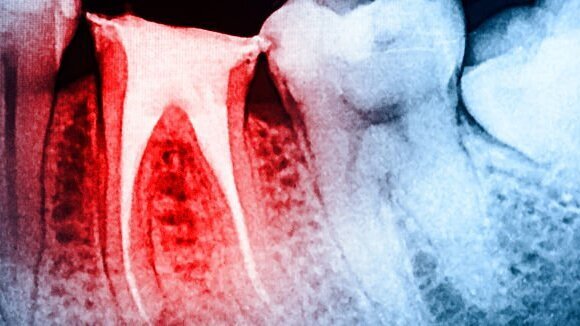

WUHAN, China: Utilizando um instrumento rotativo que é mais eficaz na preparação do canal radicular é crucial para o sucesso do tratamento endodôntico. Em uma avaliação de habilidades de modelagem de três segmentos de sistemas rotativos de níquel-titânio (NiTi), uma equipe de pesquisadores chineses verificou que um sistema de arquivo único com um movimento alternativo produziu a maior mudança volumétrica no terceiro apical do canal. Além disso, o sistema tinha o tempo mais rápido de preparo do canal dos três sistemas testados.

Os sistemas analisados no estudo foram ProTaper Universal (Dentsply Sirona), o RECIPROC single-file system (VDW) e o K3XF sistema rotativo (Kerr Dental). Para avaliar as características de modelagem de cada sistema, os pesquisadores simularam 30 canais radiculares com uma curvatura de 60° em um bloco de resina clara (Endo Trainning Bloc, Dentsply Sirona). Os canais tinham 16,5 mm de comprimento e uma seção reta de 10 mm antes da curva. Cada bloco foi aleatoriamente designado para um dos três grupos de instrumentos.

Os pesquisadores então usaram micro tomografia computadorizada para a avaliação 3-D da capacidade de modelagem dos instrumentos, transporte do canal, alteração volumétrica e habilidade de centralização, bem como parâmetros geométricos básicos da morfologia interna do dente.

Eles descobriram que o RECIPROC produziu mudanças volumétricas apicais melhoradas nos canais, comparado com ProTaper Universal e K3XF. O sistema K3XF, em contraste, apresentou menos transporte e melhor capacidade de centralização em 2 e 3 mm do forame apical do que os outros dois sistemas. No entanto, não houve diferenças significativas em relação à centralização e transporte entre ProTaper Universal e RECIPROC.

Embora o tempo de preparo do canal foi a mais curto com RECIPROC, isto pode ter acontecido porque, sendo um sistema de arquivo único, o instrumento geralmente requer menos tempo de instrumentação, salientaram os pesquisadores. Globalmente, todos os arquivos modelaram os canais simulados sem qualquer erro de modelagem significativa, concluíram.

O estudo intitulado "Uma comparação da capacidade de modelagem de três instrumentos de níquel-rotativo de titânio: Um estudo de micro tomografia computadorizada via uma técnica de contraste radiopaco in vitro", foi publicado online em 9 de janeiro no BMC Oral Health Journal.